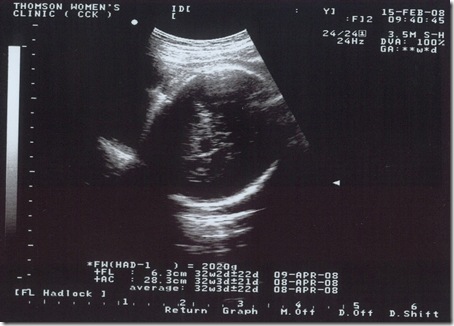

15/Feb/2008